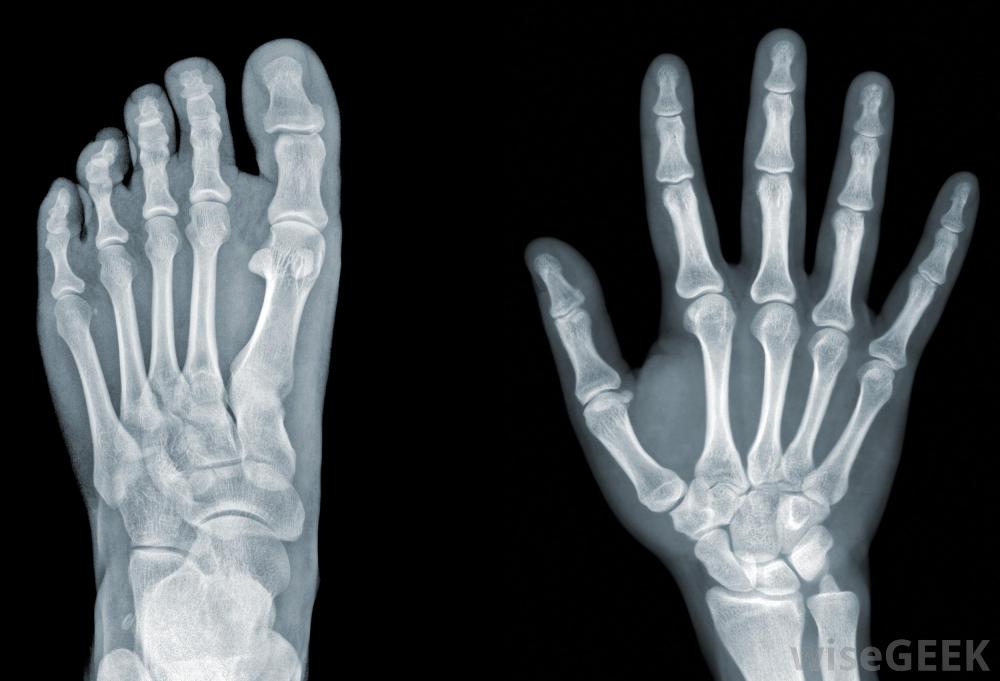

X光机提供2D打印。当需要对患者进行X光检查时,放射技术人员可以为患者准备进行该操作,并解释如何进行测试执行、设置设备并拍摄X射线图像。这需要调整设备的设置,使用屏蔽来保护患者免受过量辐射,并在拍摄图像后冲洗胶片。完成的X射线胶片可发送给患者的医生进行检查,或由放射科医生复查,在解释医学影像学研究方面接受过专门训练的医生。

X射线技师,通常称为放射技师,使用诸如X光机之类的设备来拍摄患者骨骼或身体其他内部部分的图像放射学技师在医生的监督下工作,医生会提供他们所需图像的精确指示。除了拍摄X光片,放射技师还可以保存记录,包括根据需要检查的患者胶片库。技师可以负责维护X光设备,监督X光机的使用,并在程序中佩戴辐射徽章的协助下监督人员进行X射线照射。在某些地区,"放射技师"一词不是指医疗保健提供者,但是对于一个维修和维护放射设备的人来说。在这种情况下,技术人员不参与病人护理,当设备需要注意时,请使用它。正确维护放射设备以降低过度辐射的风险并确保其正常工作非常重要。技术学校为有兴趣维修医疗设备的人员提供培训,人们也可以在工作中学习由经验丰富的技术人员指导。相比之下,技术人员可以进行更多的医学成像研究,如磁共振成像和计算机断层扫描。此外,技术人员可以参与放射性药物的管理,以用于影像学研究的示踪剂的形式用于诊断,并为需要放射治疗的癌症患者提供治疗。技术人员接受了更高的培训,而且由于他们的技能范围更广,他们的工资往往更高。